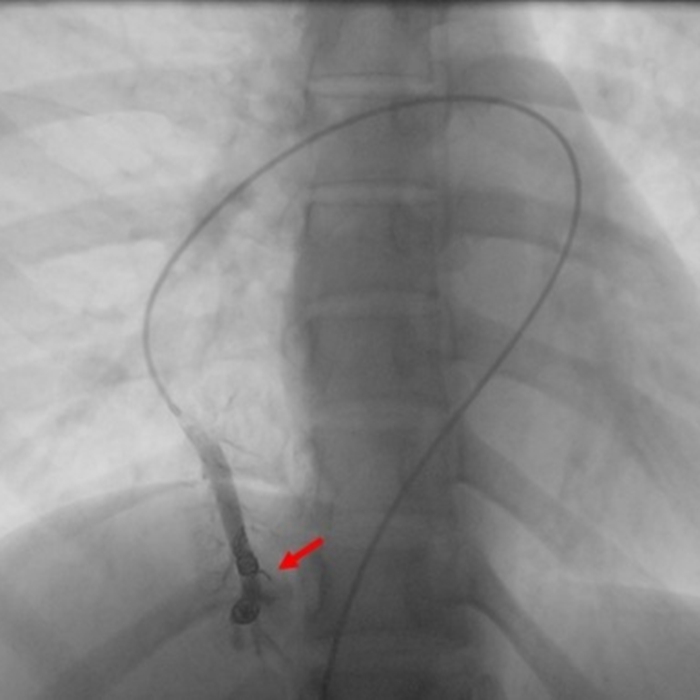

针对患者的情况,闫朝武带领柳昂、齐晨医师,在充分评估病变特征和手术路径的基础上,决定采用同步封堵的策略。术中,团队凭借娴熟的介入技术,通过微创穿刺,精准地将导丝和导管分别送至两处病变位置,并顺利实施封堵。术后即刻复查造影显示,封堵器形态良好、位置稳定,异常分流消失。患者术后恢复良好,头痛症状完全消失。